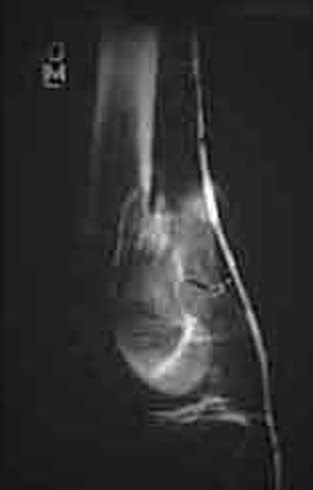

An initial injury film shows a closed supracondylar femur fracture with an arteriogram done for questionable signs of arterial injury showing a nonocclusive intimal flap of the popliteal artery. Since this arterial injury fit the published criteria for nonop observation, our orthopedic surgeons went ahead and did ORIF. 6 weeks later a F/U angio shows complete resolution of the intimal flap -- unnecessary surgery thus avoided.

This illustrates the RULE for nonocclusive arterial injuries, NOT the exception.

6 weeks later